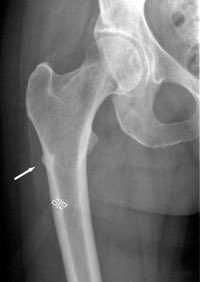

-أثبتت الدراسات أن وجود كسر بسبب الهشاشة هو أقوى دليل لإحتمال وقوع كسر آخر مع أدنى إصابة أو حركة خفيفة.

-يكون غالبا مستوى ڤيتامين د منخفض عندالمرضى الذين يتعرضون إلى كسور مع أدنى إصابة أو حركة.

مضاعفاته:قد يسبب تنخر العظم في الفك أو حدوث كسر غير عادي في أعلى عظمة الفخذ.

الخلاصة:ينبغي أخذ أدوية الهشاشه في حال وجودها والمضاعفات التي ذكرتها نادرة والفائدة تفوق تركها.في حال حدوث كسر غير عادي في عظمة الفخذ يلجأ الجراح إلى إيقاف البييفوسوفيت فورا وسيقوم بتثبيت عظمة الفخذ سواءا كان الكسر كامل أو جزئي.